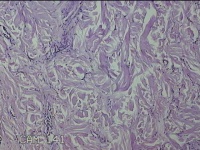

骶尾部包块

性别

男

年龄

37岁

临床诊断

骶良性肿瘤

一般病史

发现骶尾部包块10年余。

标本名称

大体所见

灰白粉红色组织3.5x1.3x1cm一块,表面带梭形皮肤3.5x1.3cm皮下见包块3x1.3cn一个,切开包块呈实性,切面灰白粉红色,质中。